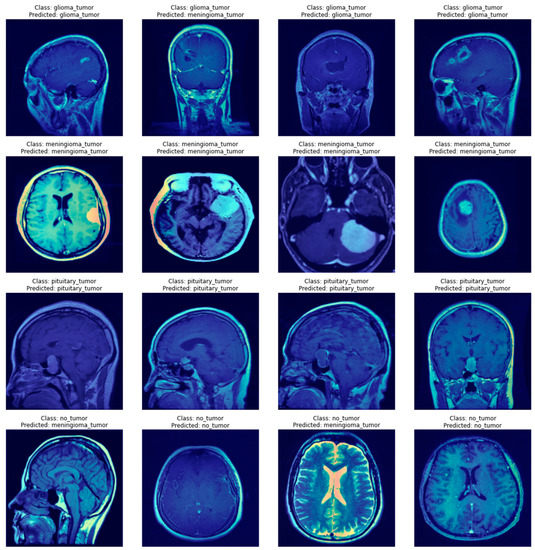

AI Approaches in Computer-Aided Diagnosis and Recognition of。Brain tumor detection and classification in MRI using hybrid ViT。NIH Uses AI to Detect Multiple Sclerosis with Human Level Accuracy。eBook使用済みです。リンパ学。A Novel Hybrid Deep Learning Model Enhanced with Explainable AI。書籍としての状態は良好です。Covering the entire spectrum of this fast-changing field, Diagnostic Imaging: Brain, fourth edition, is an invaluable resource for neuroradiologists, general radiologists, and trainees-anyone who requires an easily accessible, highly visual reference on today's neuroimaging of both common and rare conditions. World-renowned authorities provide updated information on more than 300 diagnoses, all lavishly illustrated, delineated, and referenced, making this edition a useful learning tool as well as a handy reference for daily practice.Provides authoritative, comprehensive guidance on both pathology-based and anatomy-based diagnoses to help you diagnose the full range of brain and CNS conditionsFeatures thousands of extensively annotated images, including a large number of full-color illustrations-greatly expanded since the previous edition.#brain #神経 #神経解剖 #神経内科 #脳神経内科 #脳外科 #脳神経外科#脳 #脳解剖 #頭部画像 #頭部解剖 #MRI #頭部MRI #神経画像

• AI Approaches in Computer-Aided Diagnosis and Recognition of

• Brain tumor detection and classification in MRI using hybrid ViT

• NIH Uses AI to Detect Multiple Sclerosis with Human Level Accuracy

• A Novel Hybrid Deep Learning Model Enhanced with Explainable AI